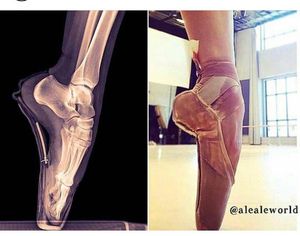

It's amazing what our bodies can handle 😎😄